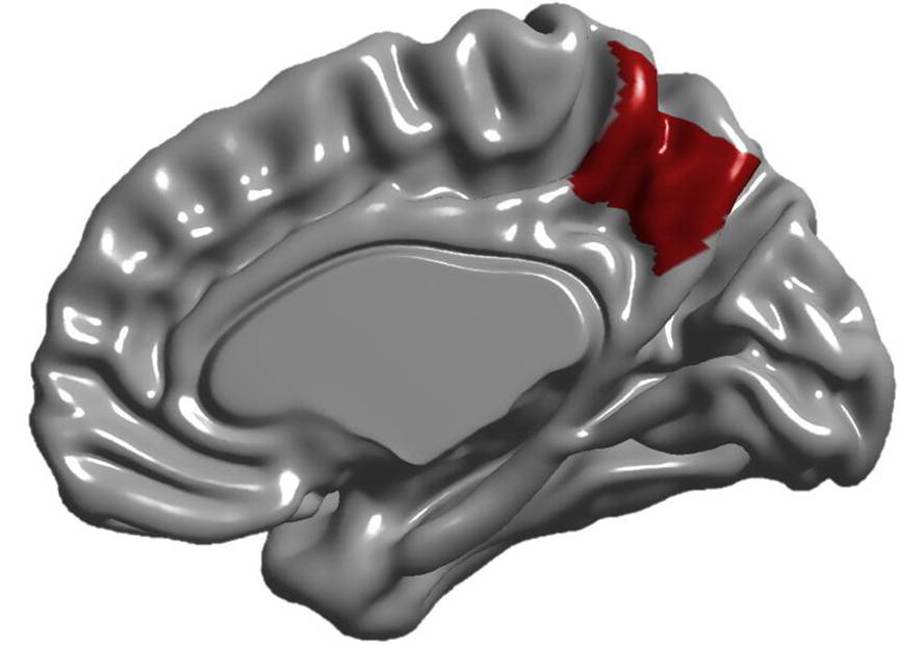

El BCI se podrá usar en el tratamiento de afecciones neurológicas como la epilepsia, lesiones medulares, ELA, accidentes cerebrovasculares y ceguera, ayudará a controlar las convulsiones y a restaurar las funciones motoras, del habla y visuales gracias a un diseño ‘mínimamente invasivo’ pero de alto rendimiento.

Que BISC esté formada por un solo chip “allana el camino para las neuroprótesis adaptativas y las interfaces cerebro-IA para tratar muchos trastornos neuropsiquiátricos, como la epilepsia”, avanza Andrea Tolias, de la Universidad de Stanford y coautor del estudio.